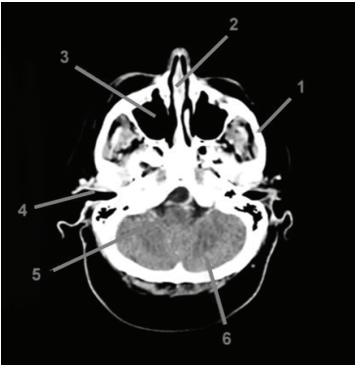

A realização de exames radiológicos permite a obtenção da imagem de formações internas do corpo, sendo possível avaliar a presença de tumores, fraturas, sangramentos, corpo estranho ou qualquer outra anomalia. Analisando a imagem abaixo, assinale a alternativa CORRETA:

Provas